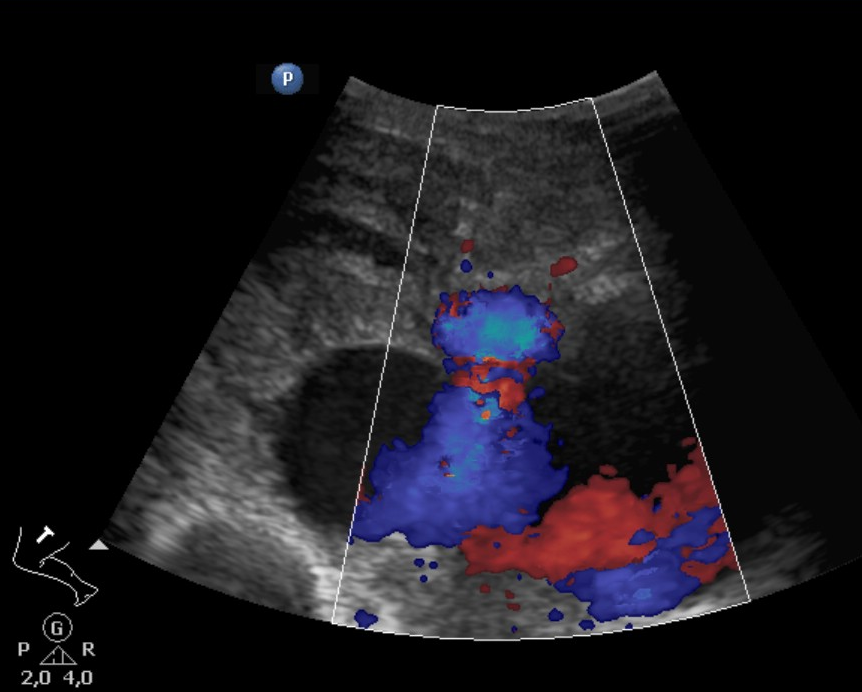

• A knife falling from a kitchen table stuck into the right thigh of an 18 year old young man. Increased femoral circumference and pulsating mass were seen. In the upper image with femoral Duplex sonography pseudoaneurysm of the femoral artery is detected

In the middle with a CT angiography the pseudoaneurysm shows contrast enhancement.

In the lower image 3D reconstruction of the CTA

11. A knife falling from a kitchen table stuck into the right thigh of an 18 year old young man. Increased femoral circumference and pulsating mass are seen. In the upper image with femoral Duplex sonography pseudoaneurysm of the femoral artery is detected In the middle with a CT angiography the pseudoaneurysm shows contrast enhancement. In the lower image 3D reconstruction of the CTA